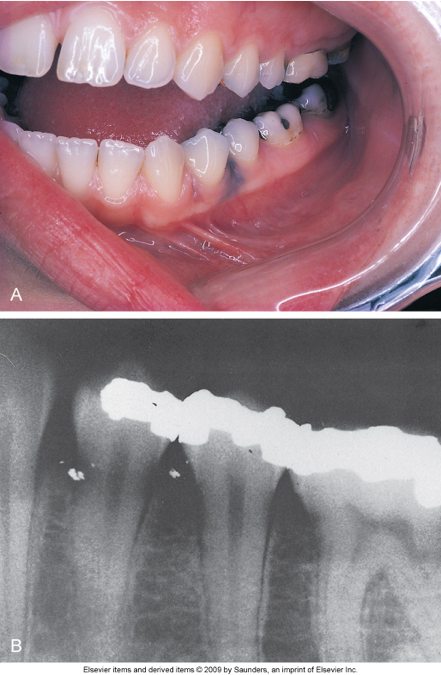

Amalgam

Amalgam tattoo